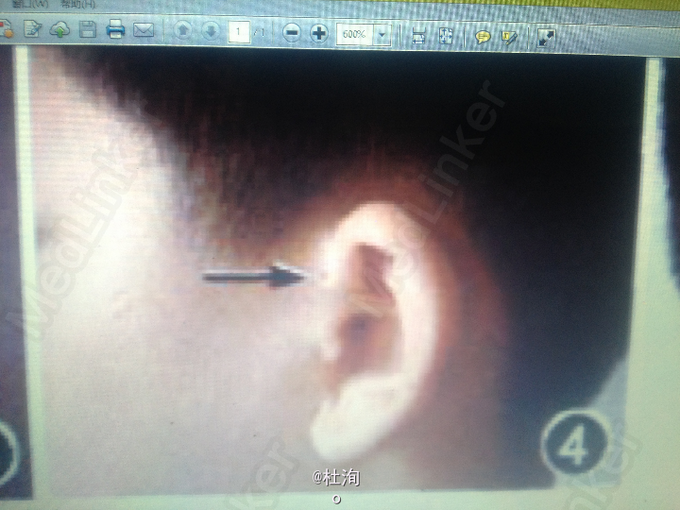

男性,12岁。自出生即发现颈部右侧瘘管及双侧耳前瘘管,语言发育迟缓。患者母亲为聋哑人,有双侧耳前瘘管,并有双侧鳃裂瘘管手术史。纯音测听结果示:双耳全聋;耳部CT示:双侧前庭导水管扩大。肾脏B超检查未见异常。患者的舅舅有双侧耳前瘘管及双侧鳃裂瘘管手术史。无听力损伤表现。肾脏B超检查结果示:右侧肾缺如。患者的外婆,聋哑人,有双侧鳃裂瘘管及双侧耳前瘘管。未能配合行进一步检查。

查体见:瘘管处挤压见清亮液体流出,患者的纯音测听检查结果:双耳中重度感觉神经性耳聋;耳部CT示:双侧前庭导水管扩大

诊断:鳃一耳-肾综合征 处理:建议行瘘管造影检查,明确瘘管所经位置,制定手术方案切除瘘管。

鳃耳肾综合征(BORS)是一种常染色体显性遗传病,因第一、二鳃弓发育异常、听力障碍、泌尿系统畸形而得名。人群中发病率约为1/40 000,而在聋哑儿童中发病率为2%。BORS的诊断标准包括听力损伤、耳部畸形、第二鳃弓瘘管或囊肿,耳前瘘管及肾脏异常,5项中符合两项且家族史阳性者或无家族史而符合以上3项者。患者及其母亲、舅舅均表现了BORS中的3个主要症状,然而其各自症状并不相同。本文摘自《中华口腔医学杂志》